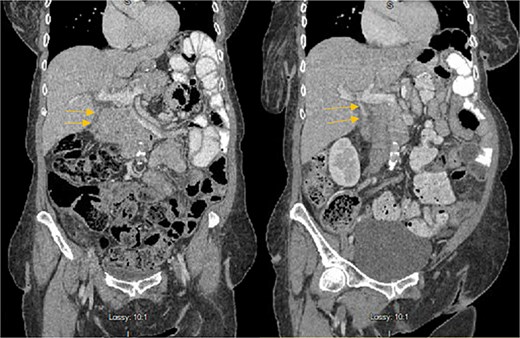

Stat CT scan showed new onset pericholecystic edema and hyperdense material within the common bile duct (CBD), not previously seen (Fig. 2). Stat Ultrasound confirmed findings of new onset acute cholecystitis (Fig. 3). Given the patient’s surgical history of gastric bypass, the decision was made to proceed with a robotic cholecystectomy with transcystic common bile duct exploration.

Hyperdense material (arrows) found in the CBD on the post-HIDA CT (right) that was not previously seen on the pre-HIDA CT on admission (left).